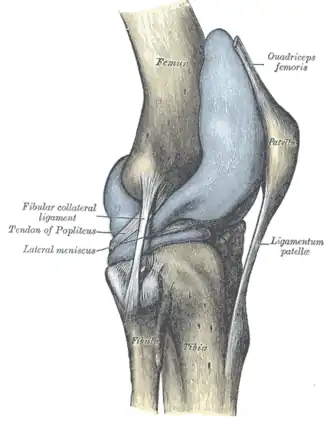

Правый коленный сустав, сбоку. | |

Крестообразные связки. Передний и латеральный вид колена.

Передний и латеральный вид колена.